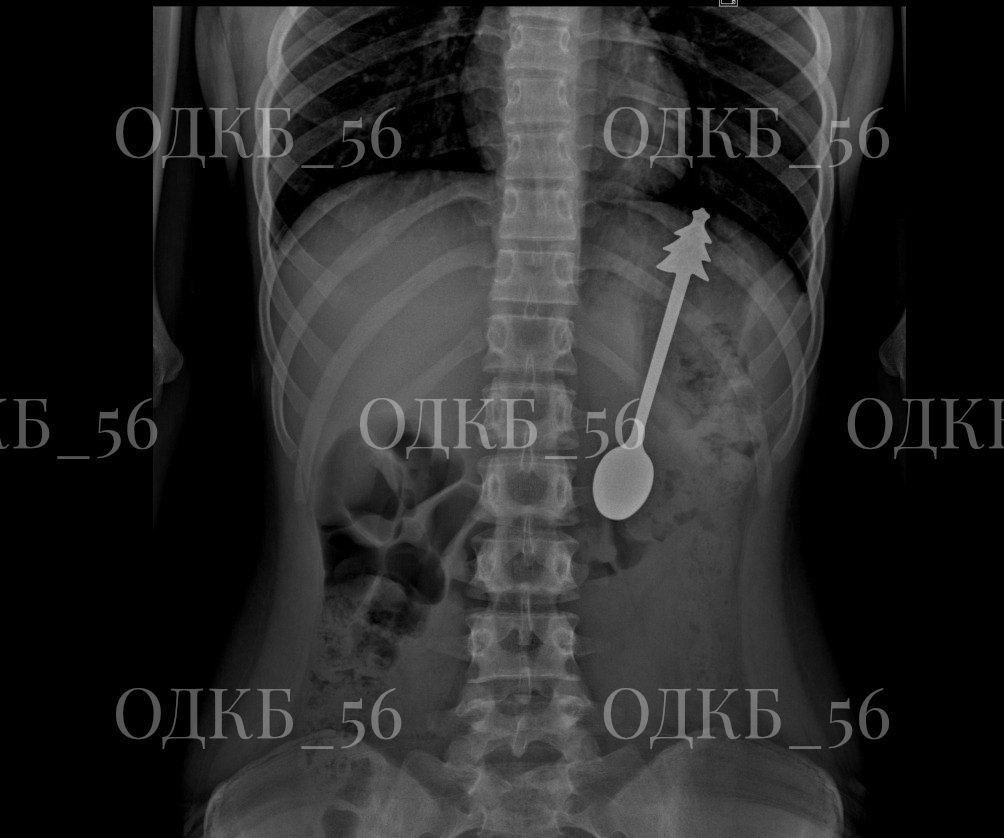

Диагностика с помощью рентгена показала, что в желудке ребенка находится ложка длиной 14 сантиметров.

Ребенка перевели в хирургическое отделение, где под общим наркозом врачи успешно извлекли ложку с помощью эндоскопа, не прибегая к разрезам.

После операции состояние мальчика было удовлетворительным, и на следующий день его отправили домой.